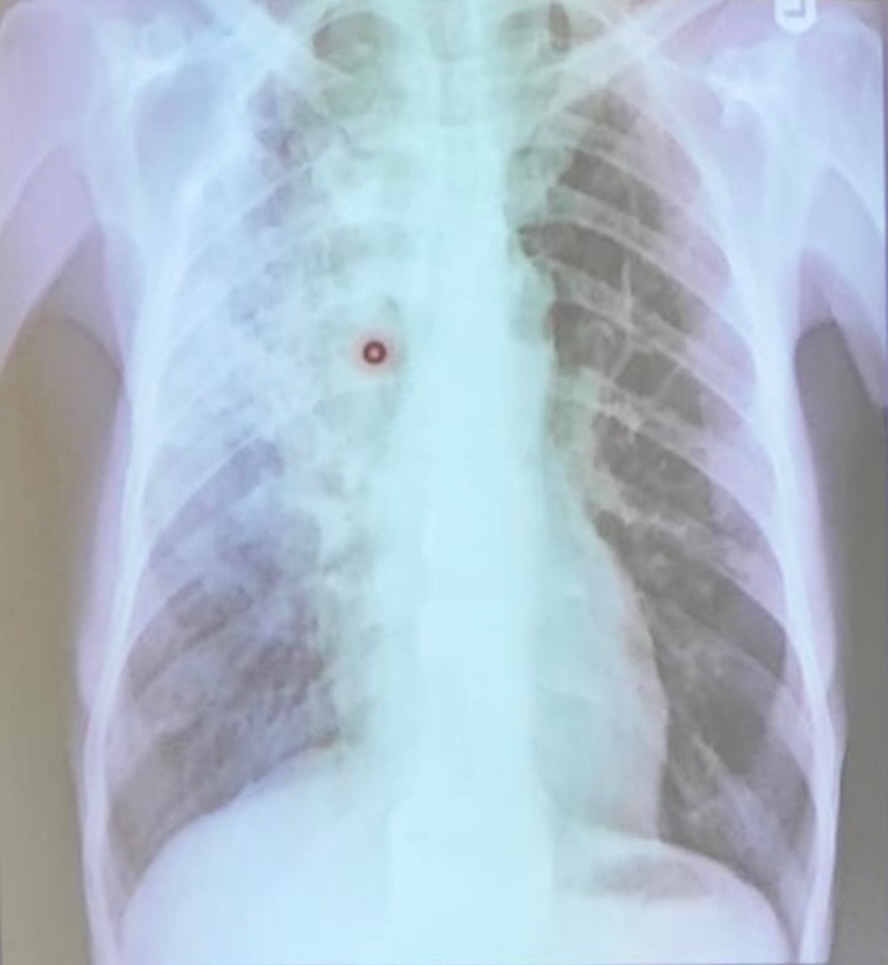

neumonía